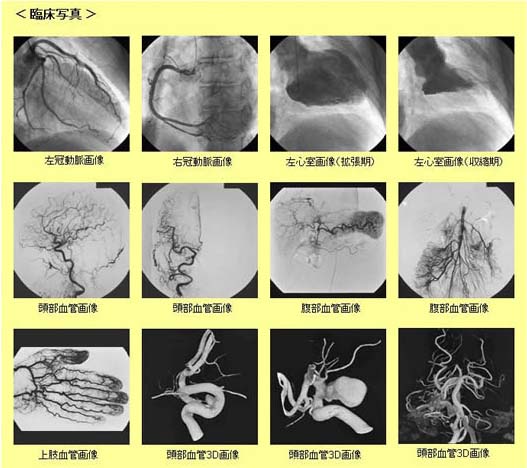

血管造影撮影装置(Angiography)

当院では、最新の血管造影撮影装置を導入し、頭部や心臓を中心として、腹部、四肢等の血管に細い管を入れて血管を映し出す血管造影検査や血管内治療を行っています。この装置により、血液の流れや血管を立体的にみることができ血管病変の早期診断、早期治療が可能になります。

血管造影X線診断装置 AlluraClarity FD20/20

血管造影X線診断装置 AlluraClarity FD20/20